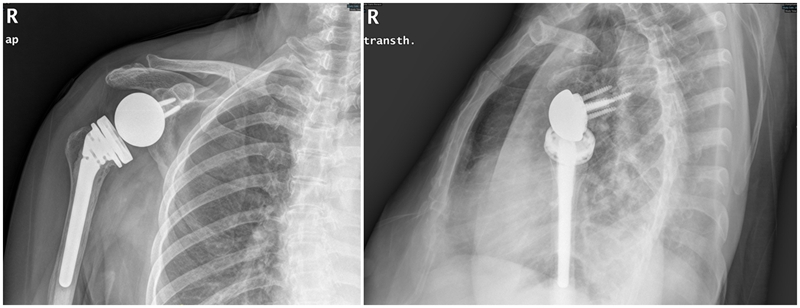

65岁女性,无明显诱因出现右肩疼痛、活动受限1年,外伤后加重2个月入院。术前右肩典型“假性瘫痪”,功能状态如图所示:

术前影像学检查示肱骨头向上移位,关节盂、肩峰和肱骨头退行性改变,典型肩袖撕裂性骨关节病(CTA)改变。

术后1年

图GIF5~7